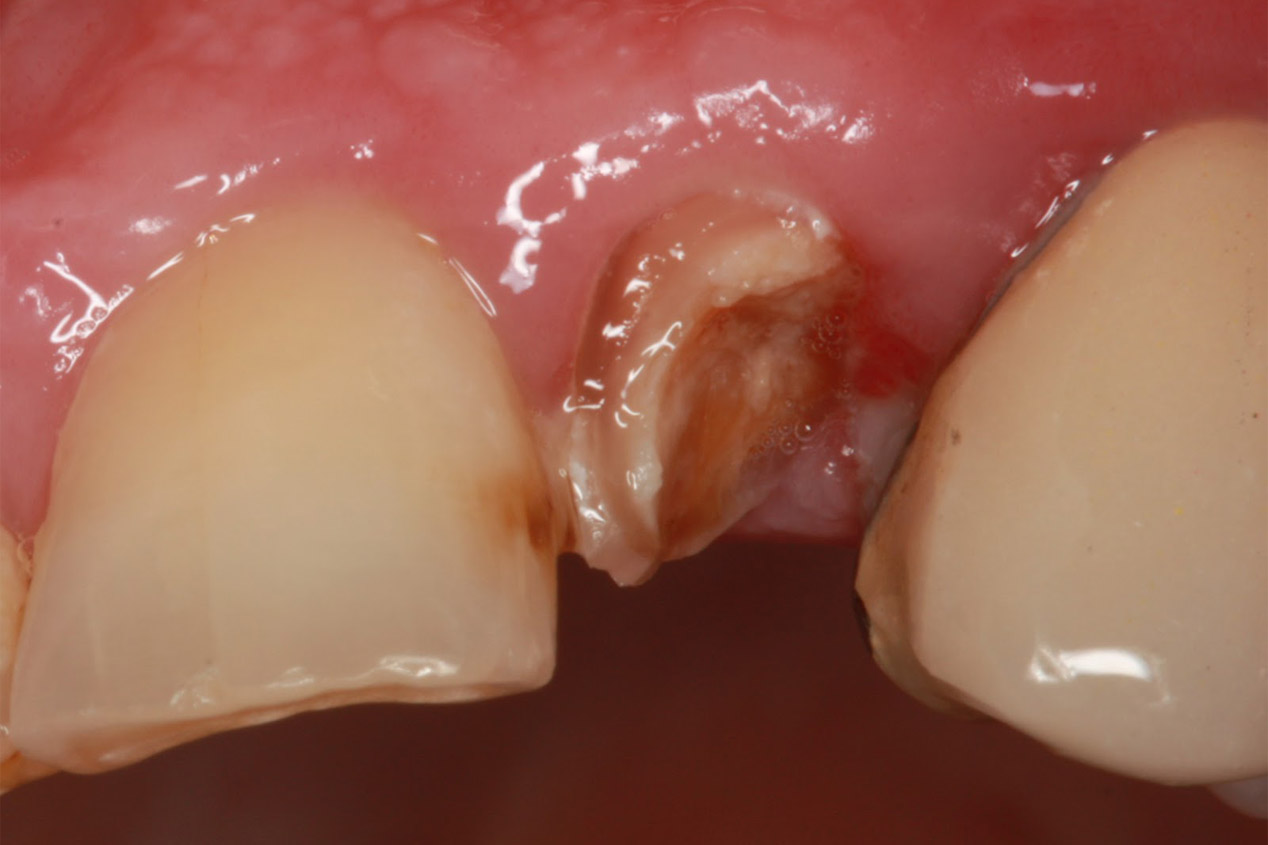

Χειρουργική αφαίρεση υπολειμμάτων ριζών

Κατά τη διάρκεια μίας εξαγωγής υπάρχει περίπτωση να σπάσει ένα κομμάτι της ρίζας του δοντιού μέσα στο φατνίο. Προκειμένου να αφαιρεθεί αυτό το υπόλειμμα, άλλοτε αρκεί μία αντιμετώπιση με απλούς χειρισμούς και άλλοτε χρειάζεται η συνδρομή της χειρουργικής. Η χειρουργική επίσης συμβάλλει στην ταχεία απομάκρυνση υπολειμμάτων ριζών σε περίπτωση όπου ένα δόντι έχει τερηδονιστεί σε τέτοιο βαθμό με αποτέλεσμα να έχουν απομείνει μόνο οι κατεστραμμένες ρίζες.